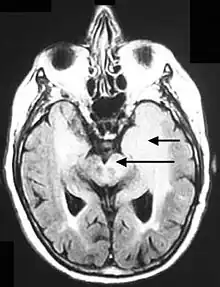

Postcontrast FLAIR of a case of meningitis. It shows enhancement of meninges at the tentorium and in the parietal region, with evidence of dilated ventricles.